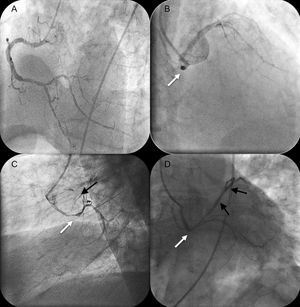

Otro varón, de 68 años de edad, con hipertensión acudió al servicio de urgencias por dolor torácico continuo. El electrocardiograma mostró un patrón de sobrecarga ventricular izquierda con un hemibloqueo fascicular anterior izquierdo; las cifras de troponina I cardiaca estaban elevados (3,6μg/l) y el paciente fue ingresado por un infarto agudo de miocardio sin elevación del ST. El dolor torácico fue refractario al tratamiento antiisquémico máximo, y se llevó a cabo una angiografía coronaria de urgencia. Durante el cateterismo cardiaco, el paciente entró en shock cardiogénico y necesitó apoyo inotrópico y ventilación mecánica. La arteria coronaria derecha era dominante y presentaba una lesión distal leve (fig. 2A), pero la ACI tenía su origen en el seno coronario derecho, con un trayecto retroaórtico (fig. 2B, flecha blanca). El tronco coronario izquierdo presentaba una importante estenosis en la parte media (fig. 2C, flecha blanca), y la arteria descendente anterior mostraba una lesión crítica proximal y estaba ocluida en el segmento medio (fig. 2C, flecha negra). Se intentó sin éxito el cateterismo de la ACI con catéteres guía XB 3,5, Judkins izquierdo 4,0 y Judkins izquierdo 5,0. Finalmente, un catéter A1 multifunción permitió realizar con éxito una angioplastia con stent del tronco coronario izquierdo y de la arteria descendente anterior izquierda (fig. 2D, flechas blancas y negras). La mejoría hemodinámica fue inmediata y permitió retirar el apoyo inotrópico y la ventilación mecánica en un plazo de 24h. La recuperación transcurrió sin incidencias y el paciente fue dado de alta con recuperación de la función ventricular izquierda. El paciente no colaboró para la realización de una angiografía coronaria con tomografía computarizada multicorte.